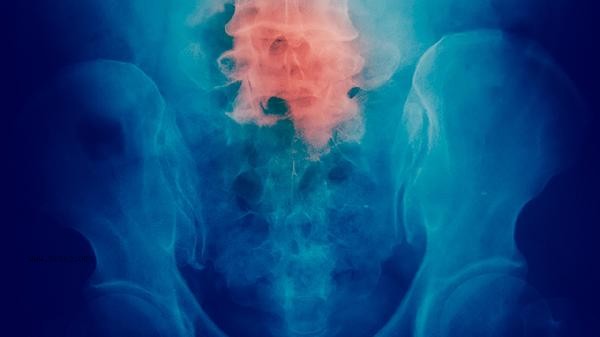

A significant increase in CEA requires caution against the possibility of malignant tumors. The positive rate of CEA in non-small cell lung cancer patients is relatively high. When the tumor invades the bronchial mucosa or undergoes distant metastasis, the CEA value may sharply increase, and a clear diagnosis should be made by combining chest CT and pathological biopsy. As the tumor volume increases and stages progress, patients with colorectal cancer may experience increased release of CEA into the bloodstream, as well as symptoms such as rectal bleeding and intestinal obstruction. When advanced gastric cancer is accompanied by peritoneal metastasis, the level of CEA often increases significantly, and pathological examination by gastroscopy is the basis for diagnosis.